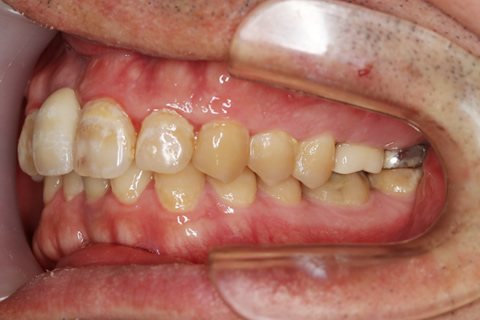

症例2

- 年齢・性別

- 57歳男性

- 治療期間

- 3ヶ月

- 抜歯

- なし

- 治療費

- 165万円

- 備考

- 左上5.6.7 及び左下6.7欠損

- 治療内容

- 左上5.6.7と左下6.7欠損部にインプラント埋入

- 施術の副作用(リスク)

- オペによる知覚障害。インプラントによる歯肉炎。インプラント脱落。